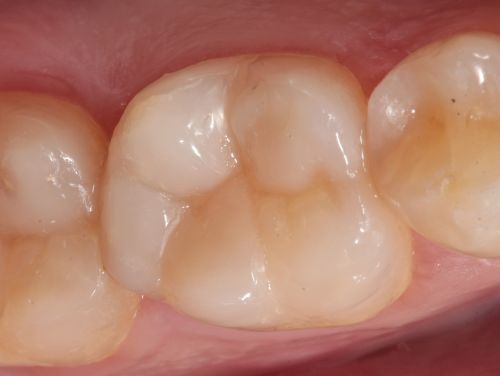

At the subsequent appointment, the temporary restoration was removed atraumatically. The indirect restoration was tried in to assess marginal fit and internal adaptation, followed by minor occlusal adjustments. The internal surface of the restoration was then conditioned by air abrasion using 50 µm aluminum oxide particles at a pressure of two bars (approximately 29 PSI), with the aim of creating micromechanical retention and enhancing the adhesion potential. The operative field was isolated, and the prepared tooth surface was subjected to airborne-particle abrasion using 50 µm aluminum oxide particles to promote micromechanical retention (Fig. 15). Subsequently, the enamel margins were etched with 37% phosphoric acid, followed by the application of a universal adhesive in accordance with the manufacturer’s instructions (Fig. 16). The same adhesive was also applied to the internal surface of the indirect restoration before cementation (Fig. 17). Voco’s Bifix QM dual-cure resin cement was then dispensed, and the restoration was seated onto the tooth surface with gentle pressure (Fig. 18). Light-curing was performed to initiate polymerization, and excess cement was carefully removed (Fig. 19). After rubber dam removal, occlusion was verified and adjusted as necessary, followed by final polishing to restore surface gloss and smoothness (Fig. 20).

Layers of Success